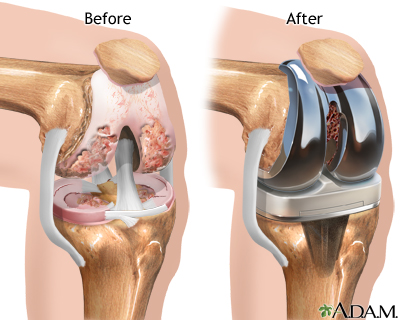

Knee Joint Replacement

Knee replacement surgery is often a last resort treatment for an injured or damaged knee joint. This procedure takes a few hours, but recovery and rehabilitation can last months. Some of the risks of this procedure are infection, nerve damage, and knee stiffness.

Knee joint replacement is a procedure that involves replacing an injured or ailing knee with an artificial joint, or prosthesis. Another name for this procedure is knee arthroplasty. Knee replacements are a very common surgery.

The prosthesis is made of metal alloys, plastics, and polymers. It mimics the function of a knee. Replacement knees can fit your needs and specifications. When selecting a prosthetic knee, your doctor will take into account your:

The procedure to remove your old knee and replace it with a prosthesis usually takes less than two hours, but recovery and rehabilitation can last months.